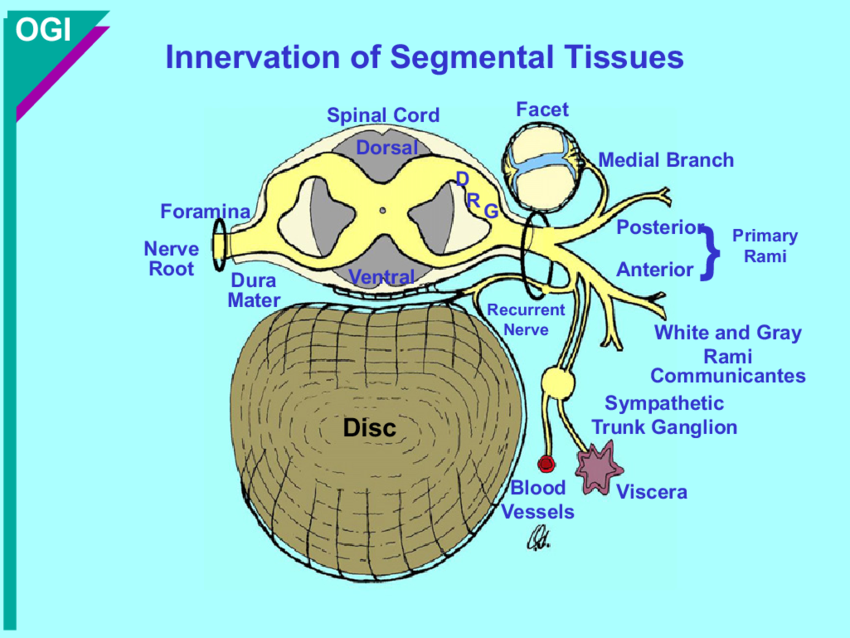

Ventral and dorsal rami

Rami communicantes

What do the ventral and dorsal rami innervate?

Dorsal: innervate back skin and muscle

Ventral: plexuses and thoracic nerves

Recurrent meningeal nerve

Supplies the facet joint, annulus fibrosus, vertebral ligaments, blood vessels and meninges